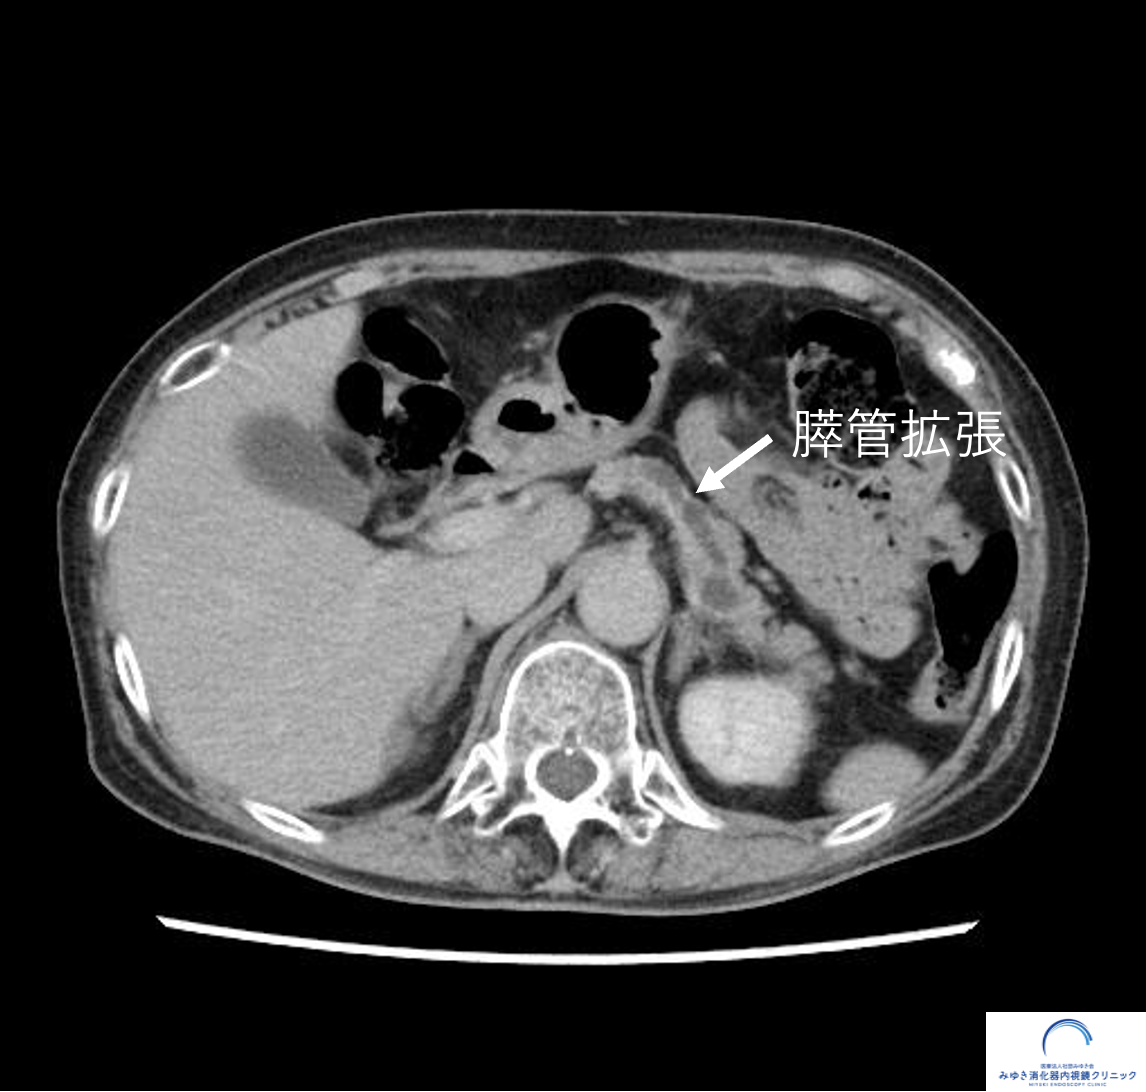

造影腹部CTでも膵嚢胞と膵管拡張を認めますが、膵管が細くなっている部位の膵臓自体が痩せているように見えます(萎縮)。

腹部CT

(平賀診療所 秋山 新二郎先生ご提供)

膵管拡張

狭くなった部分より奥側(膵臓の尾部方向)では、膵液の流れが悪くなるため膵管が拡張し、太く見えることがあります。